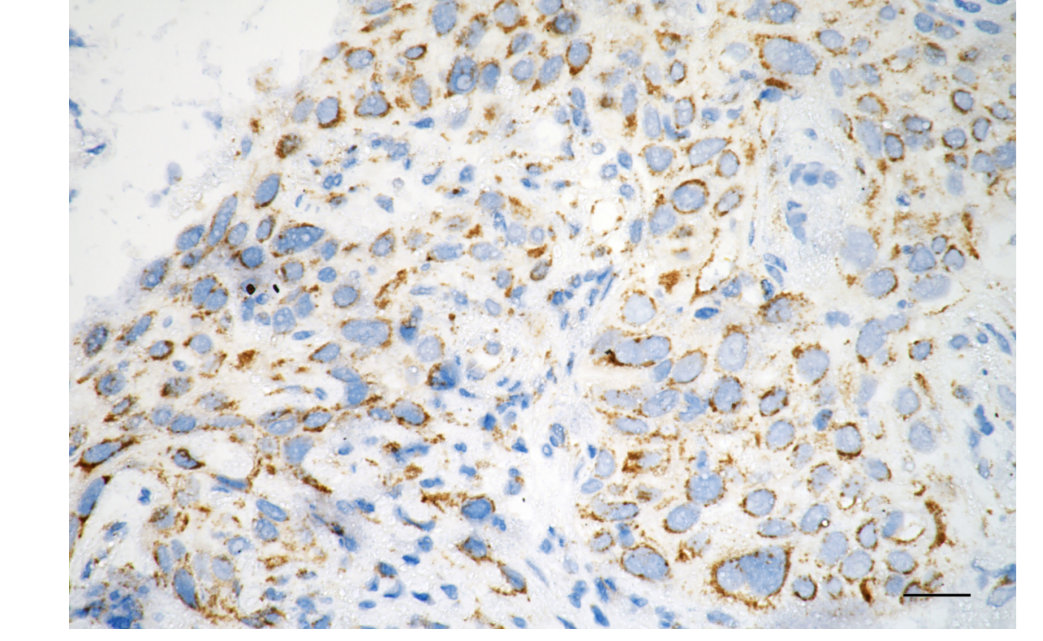

Immunohistochemistry was performed on paraffin-embedded human esophageal carcinoma using caspase 8 antibody. Antigen retrieval was done in sodium citrate buffer (pH 6.0). DAB was used for detection, with hematoxylin counterstaining. Images were acquired using a Nikon Ci-L Plus microscope (40× objective). Scale bar: 25 μm.